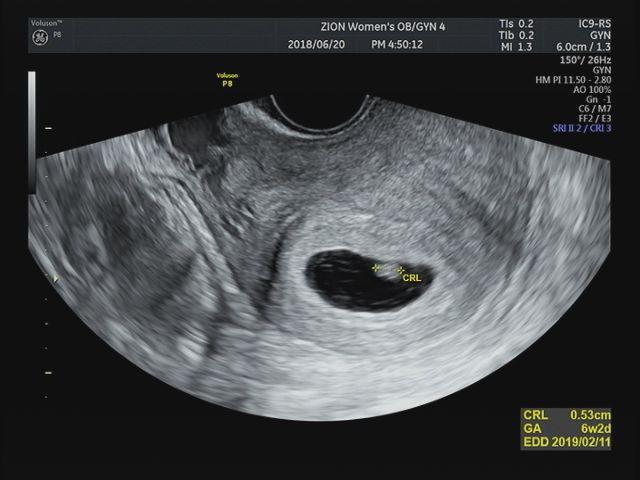

2019.01.04 +34주 6일 이날은 막달검사 하는 날! 분만 전에 채혈, 소변검사, 심전도, 엑스레이 검사를 통해...